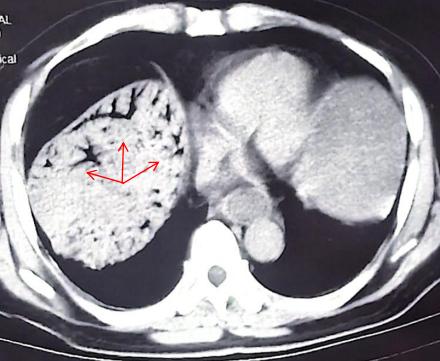

随行的朋友赶紧将他送往附近医院就诊。经急诊 CT 检查,发现他肝门静脉主干及分支存在大量气体影,呈「树枝状」,初步诊断为「门静脉积气」。这是一种危急重症,往往是由于肠道黏膜屏障破坏,肠腔内气体经破损血管进入门静脉系统所致。临床上较为少见,但一旦出现,通常提示有严重的潜在疾病,如肠缺血、肠坏死、肠梗阻、炎症性肠病或产气杆菌感染等,死亡率高达 75%。医生当即建议他们迅速转至武汉大学人民医院。

罗建飞介绍,肝门静脉积气是一种危急的影像学征象,是外科急症的「红色警报」,往往提示患者存在严重的消化道疾病。由于病情进展迅猛,若未能及时识别和干预,患者可能在短时间内出现消化道穿孔、感染性休克、多器官衰竭等致命并发症。